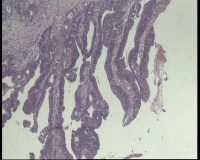

性别

女

年龄

43岁

临床诊断

结肠CA

一般病史

进镜达横结肠近肝曲,见不规则增生性肿物,环周生长,表面充血糜烂,触之易出血,肠腔狭窄,镜身无法通过

标本名称

肠镜活检

大体所见

肠镜活检4块

镜下腺体异型小,纤维间质反应,能直接报结肠腺癌吗?

可一类报告报:管状绒毛状腺癌

高-中分化腺癌。